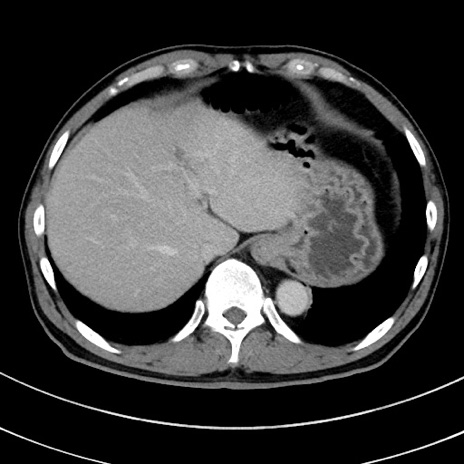

症例8(横断像)

【症例】 60歳代男性

【主訴】 黒色吐物

【現病歴】 4日前から嘔気自覚、2日前の朝食後にも嘔気あり、自分で手で嘔吐反射起こし嘔吐したところ血が混ざっていたため受診。

【既往歴】 5年前汎発性腹膜炎を伴う急性虫垂炎で手術、高血圧、前立腺肥大症、高脂血症

【身体所見】 腹部正中に手術癩痕あり 腹部平坦・軟圧痛なし膨満感あり

【データ】WBC 8400、CRP 4.54